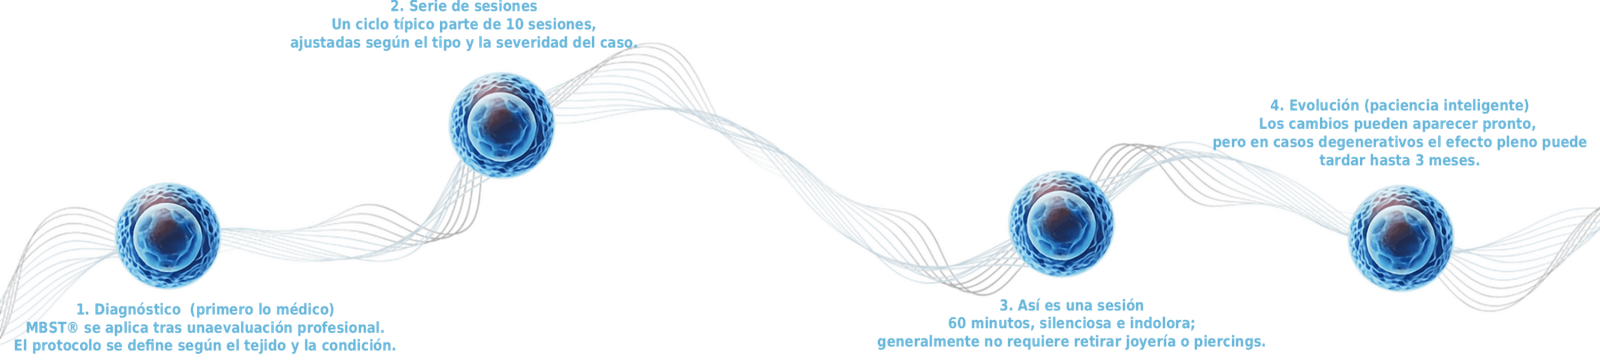

Tu tratamiento: claro, guiado y personalizado

1) Diagnóstico (primero lo médico)

MBST® se aplica tras una evaluación profesional. El protocolo se define según el tejido y la condición.

2) Serie de sesiones

Un ciclo típico parte de 10 sesiones, ajustadas según el tipo y la severidad del caso.

3) Así es una sesión

60 minutos, silenciosa e indolora; generalmente no requiere retirar joyería o piercings.

4) Evolución (paciencia inteligente)

Los cambios pueden aparecer pronto, pero en casos degenerativos el efecto pleno puede tardar hasta 3 meses.